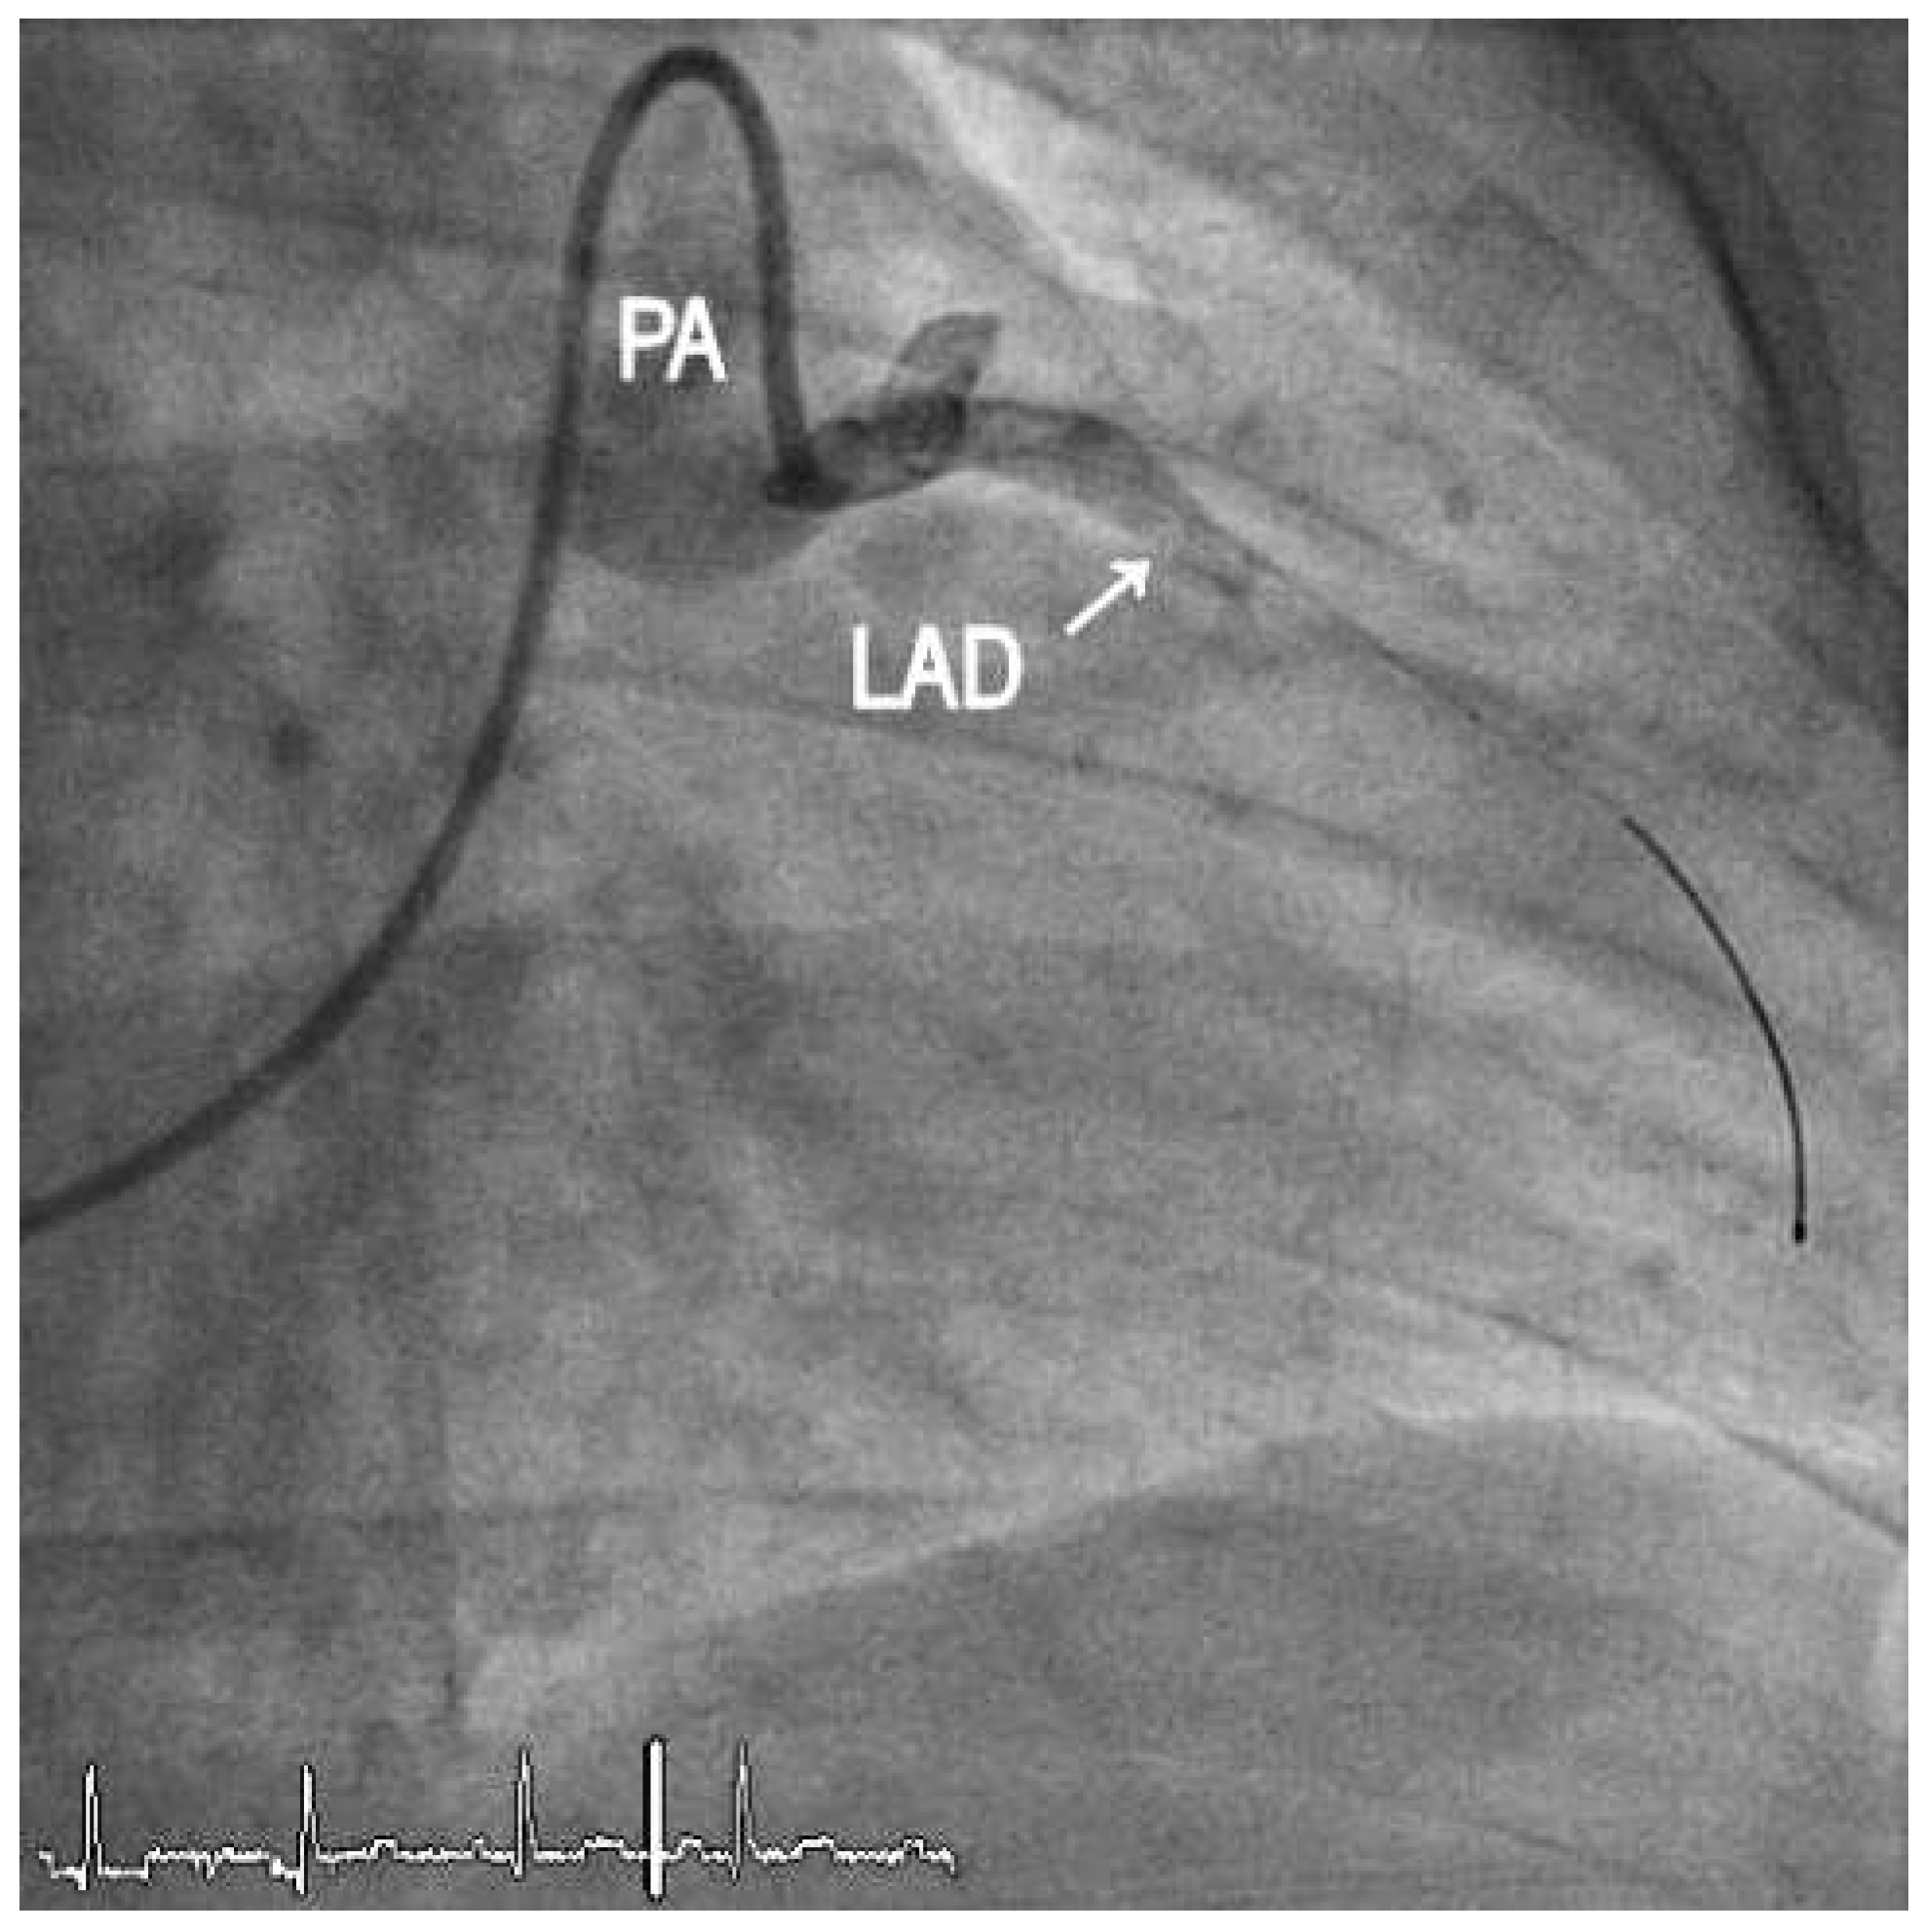

1. Case Report